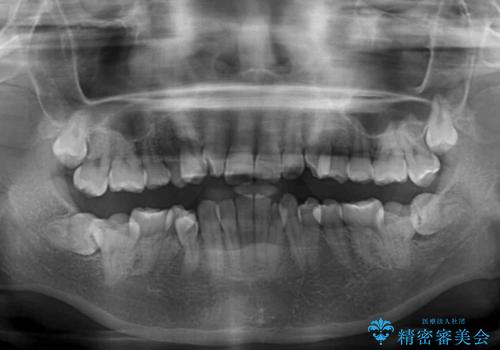

- 上下前歯のデコボコを気にして来院された患者様です。

口元の突出感はあまりなかったものの、デコボコを非抜歯で改善すると出っ歯になる可能性があるため、上下左右の第一小臼歯4本を抜歯し、ワイヤー装置にて矯正治療を行うこととしました。

口元の突出感はなかったものの、捻転や八重歯を改善するために補助装置を併用する必要がありました。